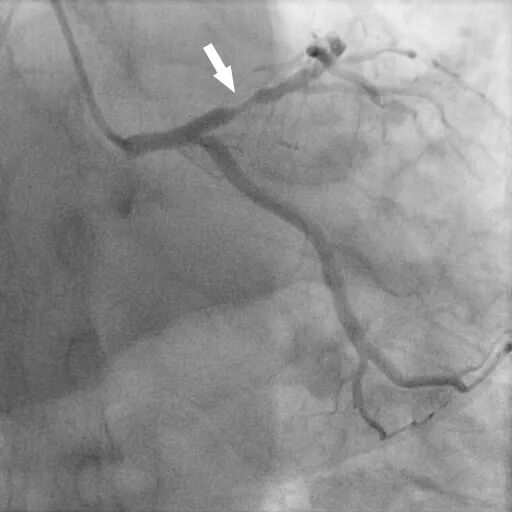

图(6)

图(7)

DSA:前降支(LAD):近段可见85%狭窄,血流TIMI 3级。PCI:于狭窄段置入支架1枚。